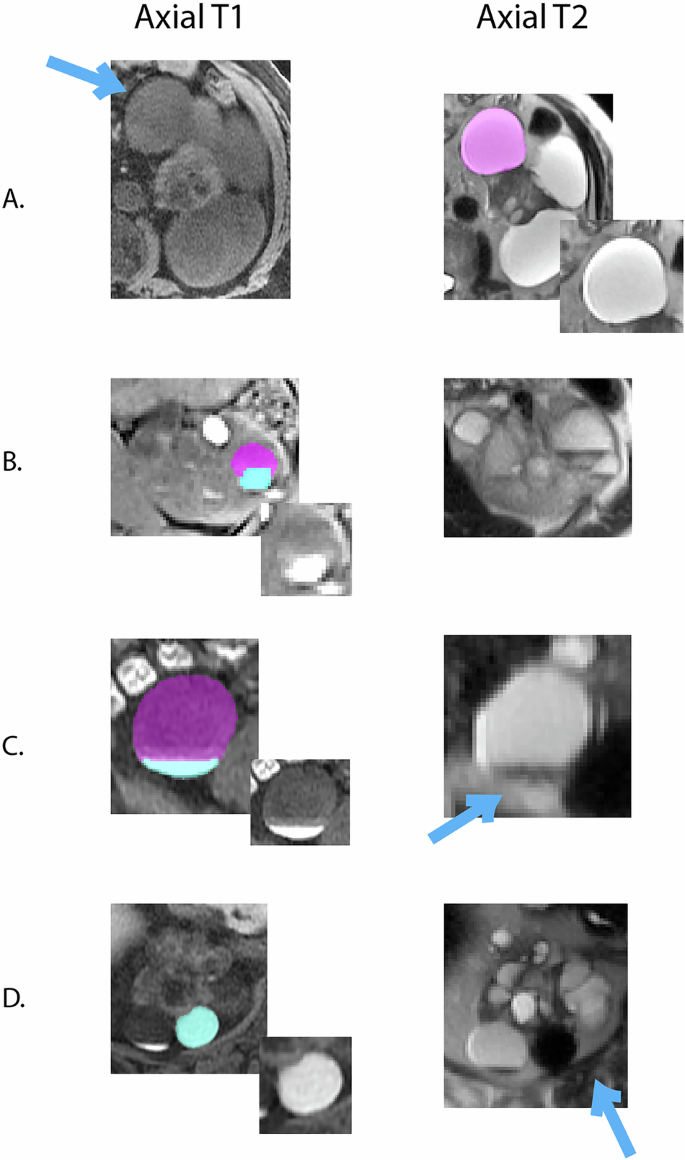

Based upon our experience reviewing more than 1000 abdominal MRI scans in over 400 ADPKD subjects, renal cysts were grouped into 5 categories (Fig. 1) as follows:

Simple homogeneously T2-bright, T1-dark cysts with imperceptible rims (Fig. 1A)

T1-bright solid within a simple T2-bright, T1-dark cyst (Fig. 1B),

Fluid-fluid level where T1-bright fluid separates from T2-bright, T1-dark simple cyst fluid at level (Fig. 1C),

Homogeneously T1-bright cyst (Fig. 1D)

Each selected cyst (blue arrow) was labeled (pink for simple fluid and blue for T1-bright fluid or DWI-bright). Labeling was performed on both T1-weighted images (left column) and T2-weighted images (2nd column). Image insets show the selected cyst without the color label. A Simple cyst T1-dark, T2-bright. B Complex cyst with solid and fluid. C Complex cyst with fluid-fluid level. D Homogeneously T1-bright, T2-dark complex cyst.